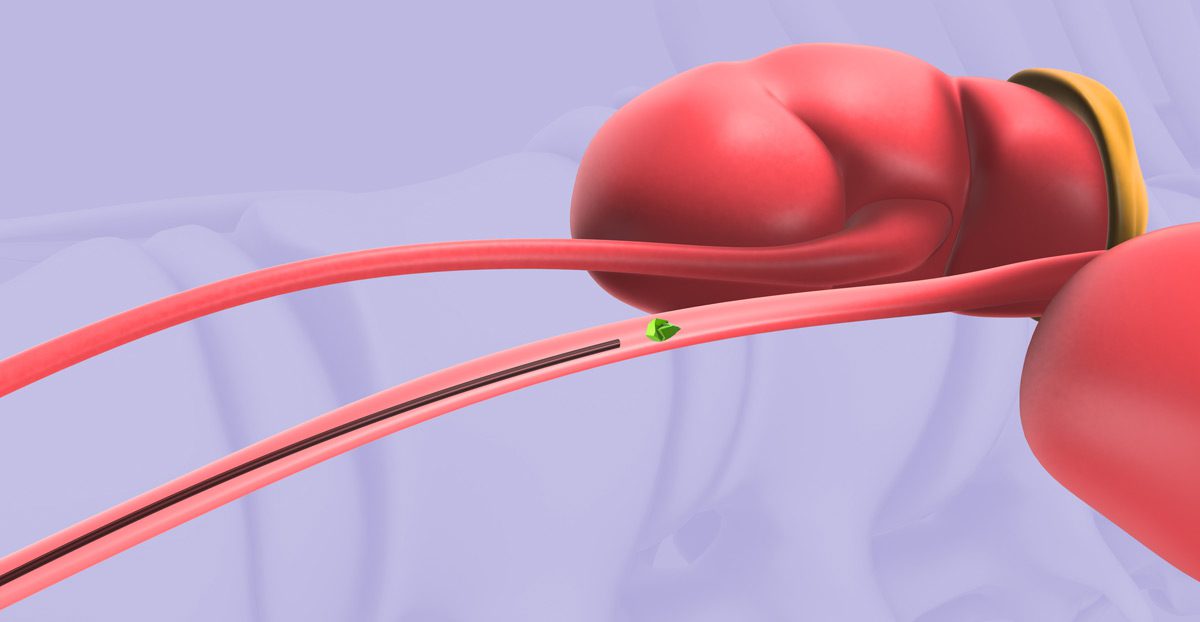

- Surgical Options: Persistent or large stones may require ureteroscopy, shockwave lithotripsy, or percutaneous nephrolithotomy (PCNL), depending on the stone’s characteristics.